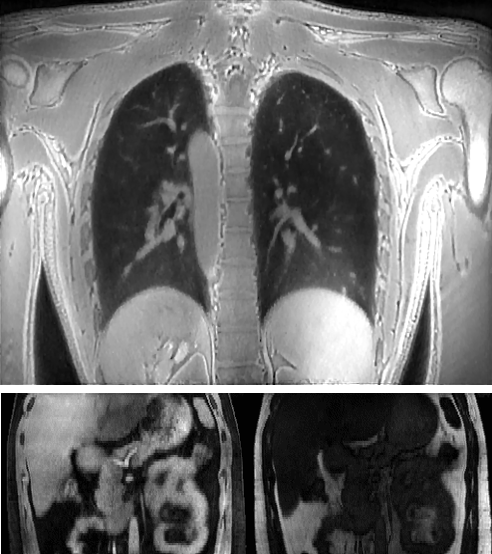

Medical imaging is now used extensively for accurate diagnosis, real-time intervention, and precision medicine. Our work has been focused on fast, high-resolution imaging augmented with functional and metabolic mapping. For example, dynamic 4D MRI under free breathing has been developed using PNCRNNs, with the reconstruction time as fast as 50 bin per second, offering substantial improvement of the image quality for dynamic golden-angle radial imaging of the abdomen. Novel imaging techniques have been developed for high-resolution whole-brain neurometabolic mapping, shedding light on in vivo molecular biomarkers for various brain diseases including stroke, brain tumor, and neurodegenerative disorders. A model-based deep learning architecture, referred to as MoDL-QSM, was developed with improved accuracy for quantifying tissue susceptibility for precise electrode implantation for deep-brain stimulation. To meet the demands for automated identification and localization of the vertebrae, pancreas, colon, lung nodules and other organs in low-dose CT, algorithms integrating local image details and global image patterns have been proposed. To extend the clinical use of nonlinear regression in medical imaging and image analysis, a deep negative correlation learning framework has been proposed to yield a deep regression of ensemble where each base model is both accurate and generalisable.

Dynamic 4D MRI of the abdomen